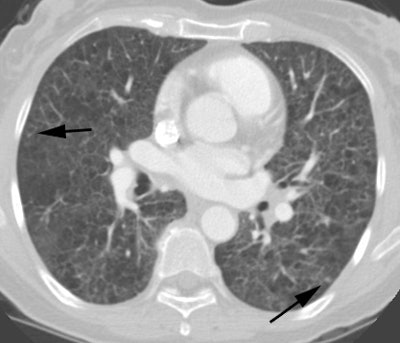

34 year old female patient presented with increasing SOB and underwent CTPE examination. PE exam revealed scattered small nodules and findings that were felt to be related to very advanced emphysema vs cysts. HRCT exam was recommended.

CT PE exam revealed no evidence of PE, but demonstrated findings suggestive of advanced emphysema versus cysts. A few small nodules were also identified within the lungs (arrow). |